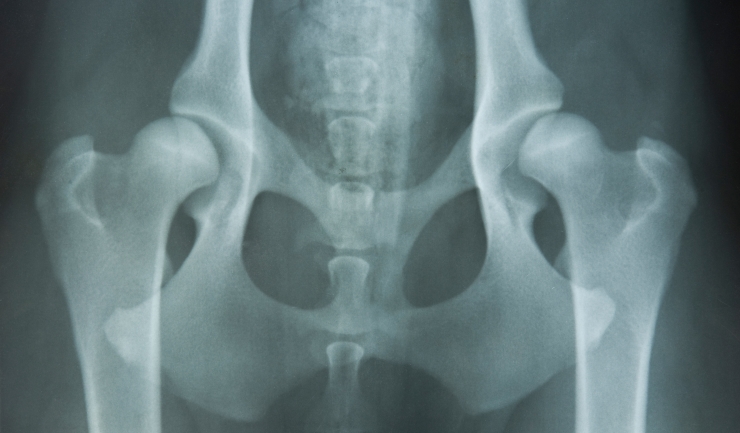

Het heupgewricht bestaat uit een ronde kop die in een kom draait. De kop en de kom van het gewricht zijn bekleed met elastisch kraakbeen en in de ruimte tussen de onderdelen zit gewrichtsvloeistof die ervoor zorgt dat de onderdelen soepel langs elkaar glijden. Het gewrichtskapsel is een stevig vlies dat om het hele gewricht heen zit en het gewricht bij elkaar houdt. Een gewrichtsband en de bekkenspieren zorgen ervoor dat de kop goed stevig in de kom blijft zitten.

Onderzoek naar heupdysplasie kan het beste gedaan worden door lichamelijk onderzoek door de dierenarts en door het beoordelen van röntgenfoto’s van de heupen. Dit kan vanaf een leeftijd van zestien weken. Voor een goede analyse moet de hond onder narcose gebracht worden. Als u vermoedt dat uw hond heupdysplasie zou kunnen hebben, bijvoorbeeld omdat hij klachten heeft of omdat het een ras is waarin HD relatief veel voorkomt, is het in elk geval raadzaam om foto’s te laten maken voor hij zes maanden oud is. Zo bent u er op tijd bij om een eventuele afwijking te laten behandelen.